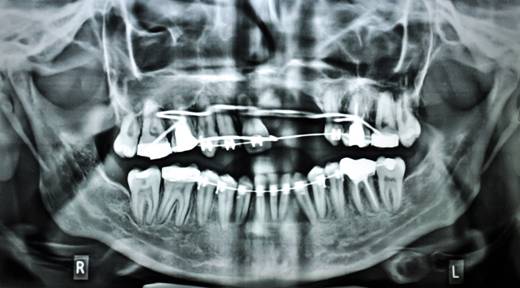

MAXILLARY LEFORT I ADVANCEMENT

BILATERAL SAGITAL SPLIT OSTEOTOMY SETBACK |